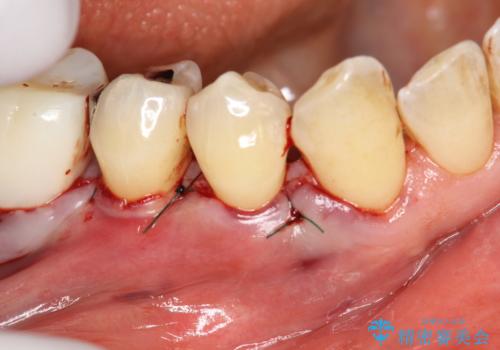

術後3ヶ月にて意図した通りに丈夫な歯肉の幅が増大し、厚みも十分に確保できました。

これで歯肉が下がることを気にせずしっかりとブラッシングしていただく事が可能になりました。